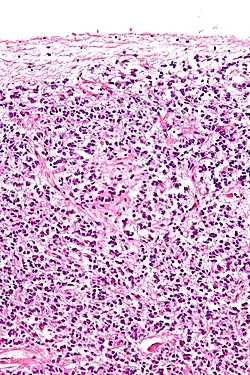

|  Cross-section of pineal gland displaying pinealocytes and other cells | |